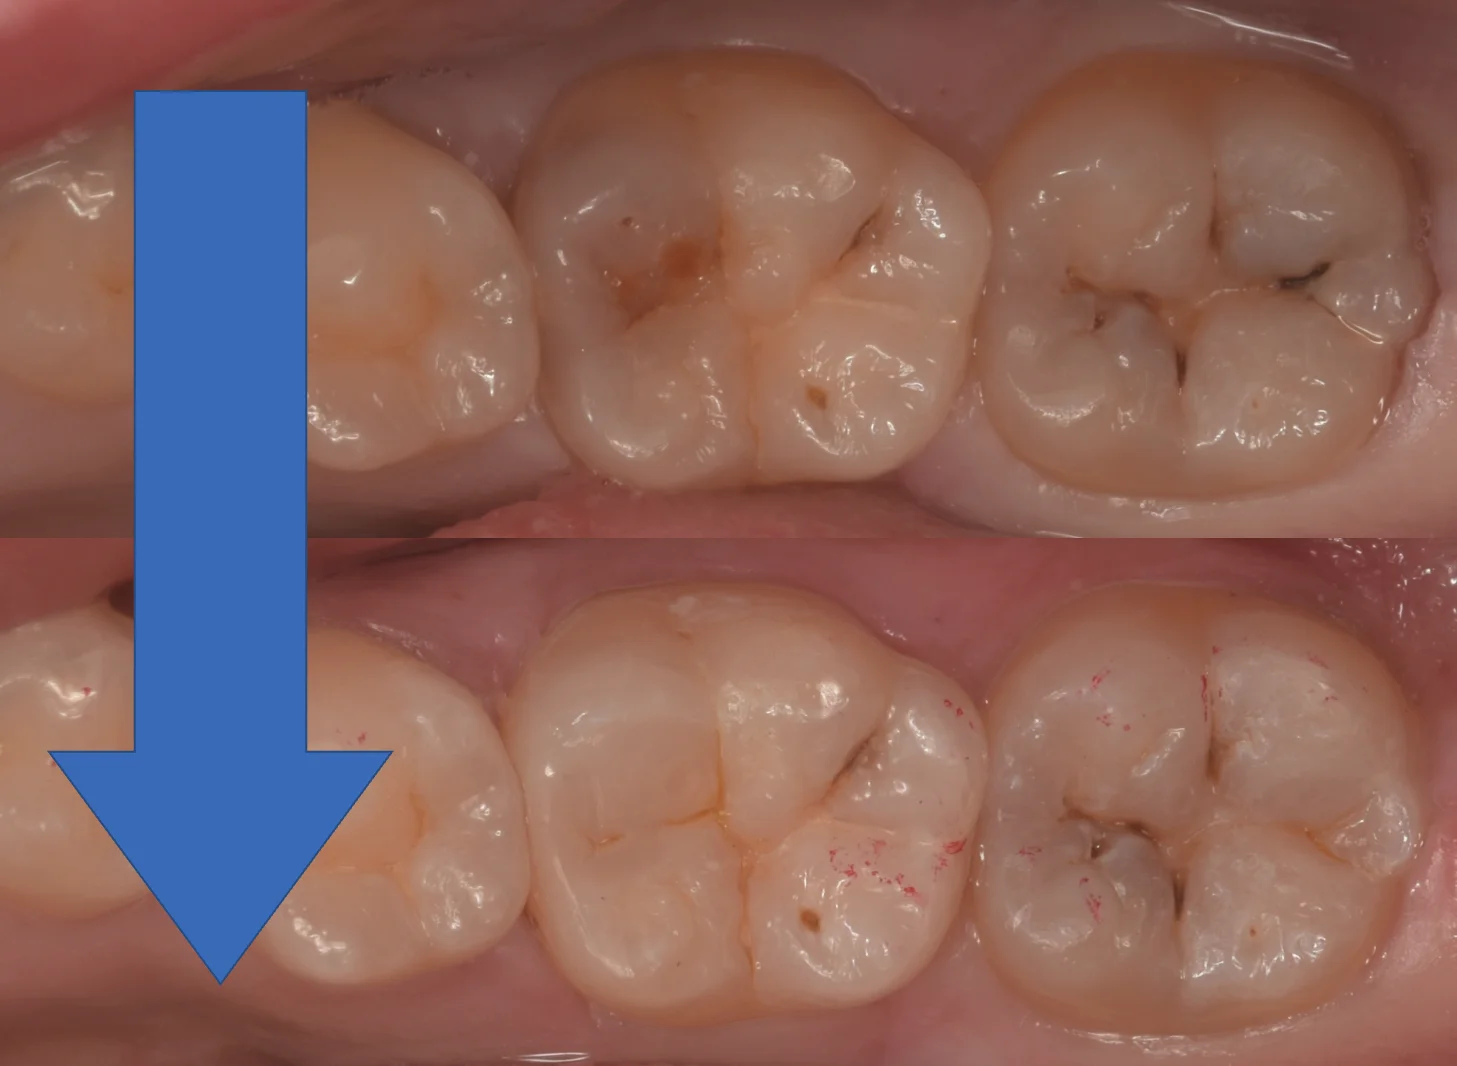

さて、詰め終わったのがこちらになります。

手前の歯との溝の色とも調和させたので、大きな違和感なく仕上げられたかと思います。

まだ乾燥によって詰めたところが浮き上がっているようにも見えますが、一週間ほどして水分が歯に戻ってくると違和感が消えてくる予定です。

術前術後の比較です。

歯を多く残せたため、ほとんど形態を同じような感じで再現することができました。

今回は他の先生に触られていない、本当に初手での治療だったため、圧倒的に歯質を温存することができたのが大きかったですね。